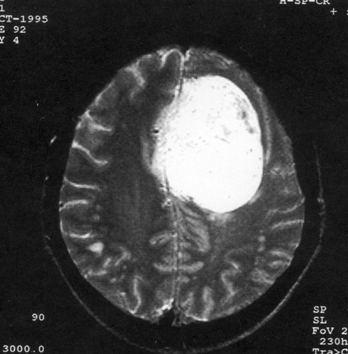

问题 病历摘要:??患者,男,40岁。发作性左下肢抽搐1年余,每次发作3~5分,每周发作1~2次。每次发作后感左下肢乏力,约半日后可自行恢复。既往身体健康。体检:神清,头顶部偏右有局限性骨性隆起(1.5×1.5cm),左鼻唇沟稍浅,伸舌居中。感觉、运动无明显异常。左浅反射减退,左下肢腱反射稍亢进,左Babinski征(-)。 下列对该患者的临床特点分析哪些是正确的?

选项 A.有Jackson癫痫发作 B.有Todd氏麻痹 C.有精神运动性癫痫发作 D.右中央前回可能有刺激性病灶存在 E.右中央后回可能有破坏性病灶存在 F.有失张力发作 G.右锥体束征(+) H.有颅内高压表现

答案 ABDG